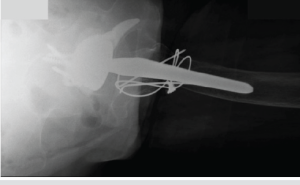

Under regional anesthesia, a Bruner incision was made over the DIP joint of the middle finger, which revealed an intact FDP insertion. Given that Leddy-Packer Type I Zone 1 avulsions are more common and can present with diffuse tenderness, initial exploration was appropriately initiated at the DIP level. A more proximal injury to the FDP tendon was suspected. The patient and his family were intraoperatively notified of these findings and recommended proximal exploration and repair of the FDP tendon. After obtaining consent from both the patient and his wife, a Bruner incision was made over the A1 pulley of the middle finger. The A1 pulley and the flexor tendons were exposed. The distal stump of the FDP tendon was located proximal to the A1 pulley. The tear was found to be in Zone 3 (Fig. 1).

Figure 1: (a) Intraoperative identification of the distal end of the torn tendon. (b) Identification of the proximal retracted end of the tendon. (c) Post-repair condition.

Friable hemorrhagic tissue was noted at the stump site. The A1 pulley was released in a longitudinal fashion. The palmar incision was extended proximally to the proximal aspect of the carpal tunnel. A synovial biopsy was obtained from the carpal tunnel and later resulted a negative for inflammatory or infectious processes. The proximal stump of the FDP was located just proximal to the carpal tunnel. The FDP tendon was then repaired primarily using Arthrex FiberLoop (Naples, FL) suture in a four-strand cruciate fashion, reinforced by 4-0 nylon suture and 5-0 polydioxanone epitendinous locked circumferential suture (Fig. 1). The presence of the tenodesis effect and restoration of the digital flexion cascade were noted on examination intraoperatively. The incision was closed, and a dorsal clamdigger splint was applied.